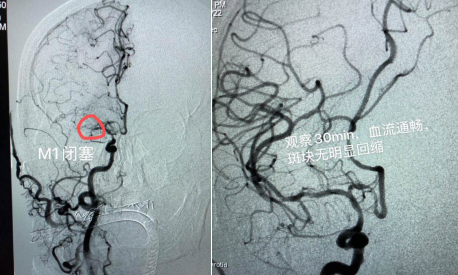

該患者男性,69歲,既往有高血壓、糖尿病、腦梗死等病史;主因“突發(fā)左側(cè)肢體活動(dòng)障礙5小時(shí)”入院;患者入院時(shí)神志嗜睡,煩躁不安,言語含糊,雙側(cè)眼球向右側(cè)凝視,雙側(cè)瞳孔等大、等圓,對(duì)光反射( + );左側(cè)中樞性面舌癱;左側(cè)肢體肌力0級(jí),右側(cè)肢體肌力5級(jí), NIHSS評(píng)分15分。入院后,立即啟動(dòng)卒中綠色通道,在頭顱CT排除腦出血后,進(jìn)行急診頭顱MRI+MRA檢查:右側(cè)顳葉梗死,右側(cè)大腦中動(dòng)脈閉塞。為進(jìn)一步明確病因,決定對(duì)患者實(shí)施腦血管造影+備支架機(jī)械取栓術(shù),盡最大努力挽救患者生命。時(shí)間就是生命!腦病科丁煜主任緊急與患者家屬溝通病情,取得了家屬的同意。在急診科、放射科、麻醉科、重癥監(jiān)護(hù)室、檢驗(yàn)科等多學(xué)科協(xié)作下,以腦病科邢錫熙主治醫(yī)師為首的神經(jīng)介入治療組迅速完成術(shù)前準(zhǔn)備,于入院內(nèi)1小時(shí)進(jìn)入導(dǎo)管室穿刺造影,發(fā)現(xiàn)患者右側(cè)大腦中動(dòng)脈M1遠(yuǎn)端閉塞,遂行支架機(jī)械取栓術(shù),一次性開通血管;發(fā)現(xiàn)大腦中動(dòng)脈重度狹窄,在藥物維持血流無效的情況下,當(dāng)機(jī)立斷行球囊擴(kuò)張,血管順利3級(jí)開通,觀察半小時(shí)血流通暢。

術(shù)前血管閉塞                  術(shù)后血管3級(jí)開通

術(shù)后患者轉(zhuǎn)入重癥監(jiān)護(hù)室,術(shù)后6小時(shí)患者意識(shí)完全清醒,術(shù)后3天右側(cè)肢體肌力恢復(fù)至3級(jí),轉(zhuǎn)入普通病房,經(jīng)過半個(gè)月的精心治療,患者右側(cè)肢體肌力基本恢復(fù)正常,康復(fù)出院。